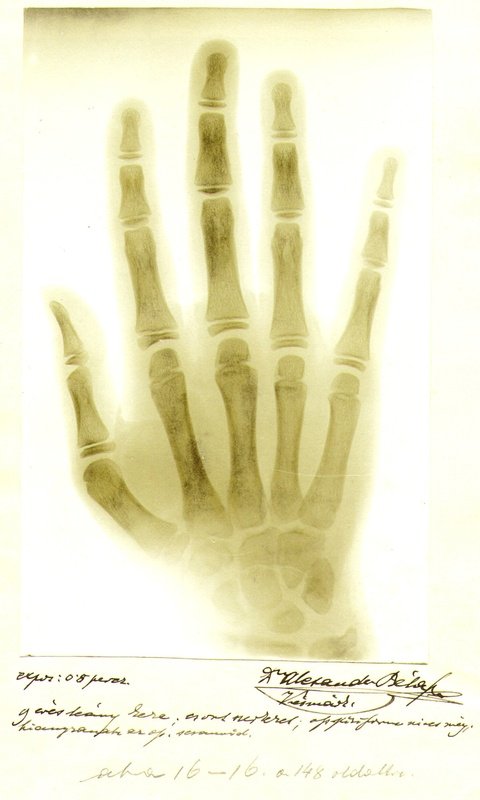

Po prvej správe o lúčoch X odcestoval do Würzburgu, kde sa stretol s W. C. Röntgenom, aby sa podrobne zoznámil s jeho vynálezom. Špecializoval sa na röntgenológiu a už v roku 1896 prvý v Uhorsku robil röntgenologické pokusy.

Jeho prvá snímka bola zhotovená už v roku 1898. Jeho prístroj je uložený v Múzeu v Kežmarku. V roku 1897 po zakúpení nového aparátu robí stereoskopické snímky.

Dr. Alexander vypracoval metodiku tzv. plastického snímkovania a založil plastickú röntgenológiu, v čom mu patrí priekopnícke svetové uznanie. Zhotovil sériu snímok embryonálneho vývinu človeka a podrobne rozobral vývoj pľúcnej tuberkulózy.

Informácie o svojich výskumoch podal na zasadnutiach Spolku uhorských lekárov v Budapešti, kde prednášal o osifikácii kostí, čo dokumentoval svojimi snímkami. V roku 1905 sa zúčastnil na prvom zjazde röntgenológov, kde bol poverený predsedaním a jeho štúdie o röntgenologickej problematike boli publikované v nemeckých i anglických odborných časopisoch.

Jeho prvý röntgenový snímok pochádza z roku 1898.V roku 1897 začal robiť stereoskopické (priestorové) röntgenové snímky. Vypracoval metodiku plastického (stereoskopického) snímkovania a založil plastickú röntgenológiu, za čo mu patrí svetové uznanie ako priekopníkovi. Zhotovil sériu röntgenových snímok embryonálneho vývinu človeka a podrobne analyzoval vývoj pľúcnej tuberkulózy.

Röntgenový prístroj, ktorý prof. Alexander nainštaloval vo svojej kežmarskej ordinácii, bol prvým röntgenovým zariadením na Slovensku. Zaoberal sa aj röntgenovou diagnostikou obličiek a močových ciest a štúdiom kontrastných látok. Ako jeden z prvých si uvedomil nielen diagnostické, ale aj terapeutické využitie röntgenových lúčov (rádioterapia).